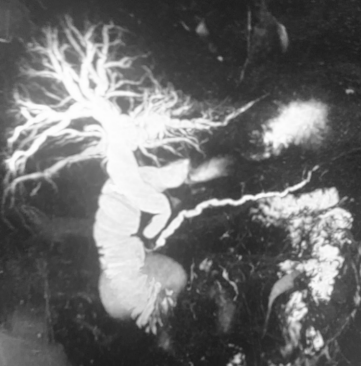

Quanto ao exame acima, realizado em paciente ictérico, é correto afirmar que o(a)

diagnóstico provável é o de tumor periampular.

diagnóstico de coledocolitíase é o mais provável.

CA 19.9 nessa situação pode não ser decisivo na elucidação diagnóstica.